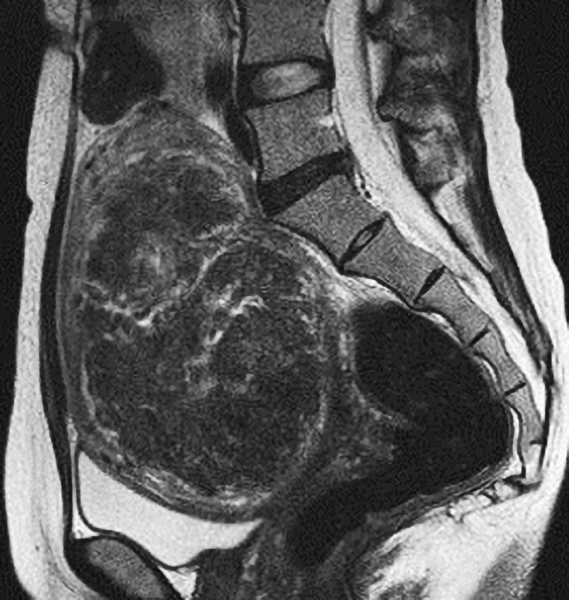

以下のMRI画像は下腹部縦切りの断面で画面右が背中です。

おへそ近くまで大きくなった13cmの筋腫でした。開腹手術の予定でしたが、子宮鏡で摘出し妊娠出産しました。

「子宮鏡で取れるのは4~5cmまで」と思っている医師が多いです。